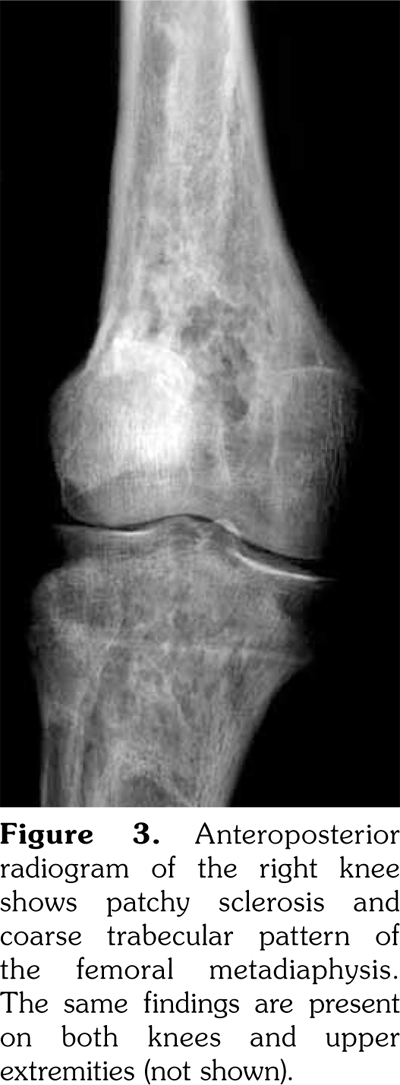

A 51-year-old male patient admitted to our outpatient clinic with complaints of flank pain and fatigue. He had a history of renal stones and peripheral arterial disease. He had a medically unmanageable hypertension. Blood pressure was 200/110 mmHg. Serum creatinine level was 1.2 mg/dL. He was evaluated with contrast- enhanced multislice computed tomography. Along with small calyceal stones, there was bilateral, quite symmetrical perinephric ''rind-like'' soft tissue infiltration. Right kidney was atrophic but still functioning without pelvicalyceal contrast excretion. The soft tissue infiltration obliterated both renal hila and caused proximal ureteral stenoses with mild calyceal dilation on the left side (Figures 1 and 2). Distally, the ureters were normal. Incidentally, abdominal aorta, common iliac arteries, proximal celiac trunk, and proximal renal arteries were noticed to appear “coated” with subtle perivascular tissue infiltration. An endovascular aortoiliac stent-graft was in place. He rejected any further diagnostic intervention after he presented with a blood creatinine of 2.2 mg/dL. He underwent an unenhanced computed tomography examination with the same findings before. Renal scintigraphy revealed a non-functioning right kidney. Perinephric soft tissue infiltration was considered as the differential diagnosis of ECD. Direct radiographies of the extremities were obtained. All of the long tubular bones showed diametaphyseal cortical and patchy medullary sclerosis reinforcing the diagnosis of ECD (Figure 3). The patient underwent right nephrectomy for the control of hypertension and a double-J stent was placed on the left side for the relief of ureteral obstruction. The nephrectomy specimen showed the typical histological features of ECD. Serum creatinine level dropped to the borderline values after the operation and his blood pressure was in the normal range with medications. The pathological analysis of the nephrectomy specimen revealed an inflammatory infiltrate formed by foamy histiocytes that were positively stained for CD68 and neutrophilic aggregates which confirmed the preoperative diagnosis (Figures 4 and 5). A written informed consent was obtained from the patient.

The X-ray changes that are considered to be pathognomonic and found in almost all patients are dia-metaphyseal osteosclerosis bilaterally and symmetrically in the tubular bones of upper and lower extremities.(5) They also show an increased uptake of tracer on Technetium 99m bone scintigraphy.(4) These bone changes may be misdiagnosed as Paget’s disease, lymphoma, sarcoidosis, metastases, or lipid storage diseases.(6,7)

In our case, computed tomography findings suggested retroperitoneal fibrosis but the infiltrate did not involve the vena cava and the paraaortic infiltration was circumferential instead of sparing the posterior aspect of the aorta. Also, the perinephric infiltration was far more striking than the perivascular space which is inconsistent with retroperitoneal fibrosis. Therefore, the differential diagnosis consisted mainly of processes involving perinephric and perivascular spaces, namely, lymphoma, retroperitoneal fibrosis, and ECD. The diagnosis of ECD was strongly suggested with the radiographic findings of the extremities which revealed symmetrical dia-metaphyseal osteosclerosis.